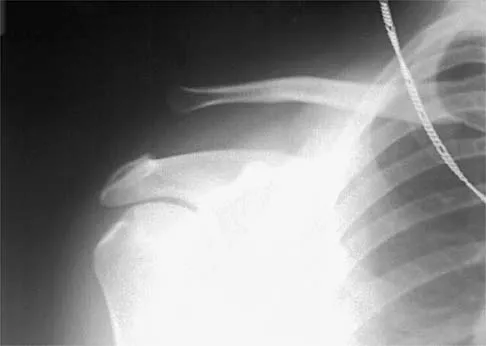

Figure 7 shows the radiograph of an 18-year-old hockey player who sustained a shoulder injury during a fall into the side boards. Examination reveals a significant prominence at the acromioclavicular joint. Management should consist of

Explanation

The radiograph shows a type V acromioclavicular separation with greater than 100% superior elevation of the clavicle. This finding implies detachment of the deltoid and trapezius from the distal clavicle. Because of severe compromise of function and potential compromise to the overlying skin, surgery is the treatment of choice for type V acromioclavicular separations. During reduction and repair, meticulous repair of the deltotrapezial fascia will also aid in securing the repair. Nuber GW, Bowen MK: Acromioclavicular joint injuries and distal clavicle fractures. J Am Acad Orthop Surg 1997;5:11-18.